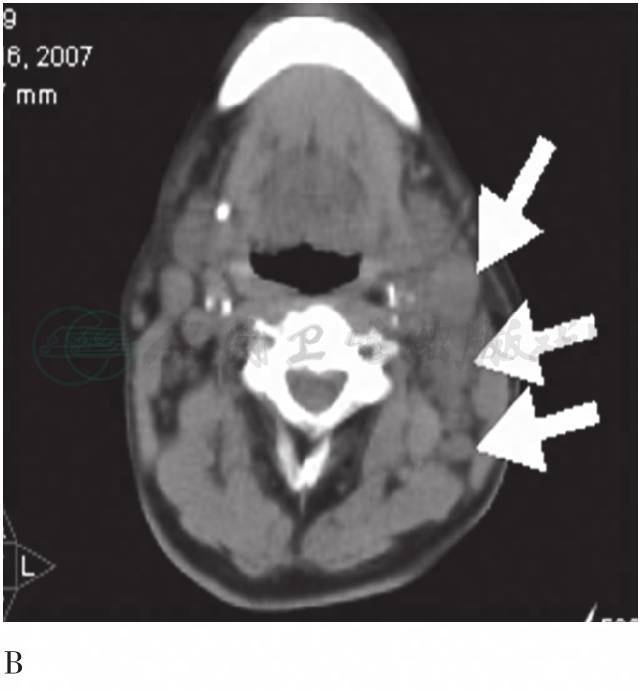

图2 FDG PET/CT颈部横断层图

A. PET图像;B. CT图像 箭头示左颈多发代谢活性增高的肿大淋巴结,淋巴结内放射性分布均匀,未见钙化、融合等征象;椭圆内高代谢处为右侧颈部血管影